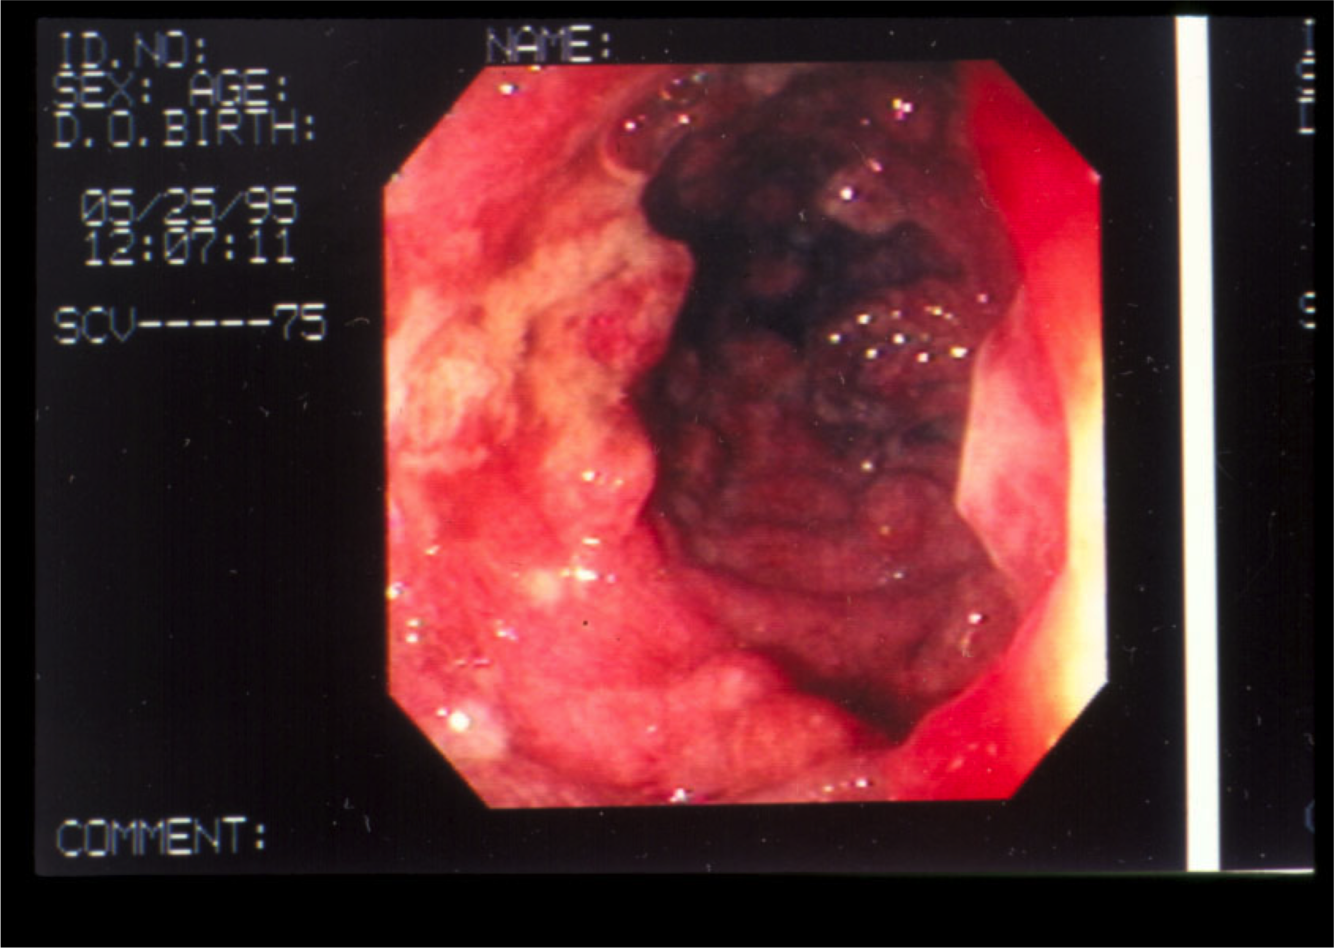

What’s this? Notable features?

Severe ulcerative colitis.

Note erythema, easy friability (would bleed easily), ulceration, exudates, circumferential involvement